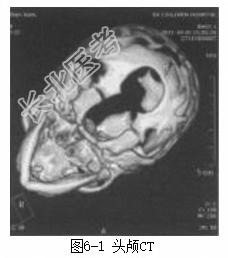

患儿男性,1月龄。因“出生后发现枕部肿物1个月”入院。患儿出生后家长即发现其枕部有一肿物,约“核桃”太小,随患儿生长,肿物逐渐增大,家长发现患儿哭闹对肿物可略增大,安静睡眠时又略缩小,至今无破溃、流液。发病以来,患儿食欲好,大小便正常,不伴有呕吐、肢体抽搐等情况。体格检查T37℃,R36次/min,P116次/min,BP78/神志清楚,头围40cm,前囟平软,枕部中线处可见一大小约5cm×5cm×4cm的肿物,表面无毛发生长,质软,囊性感,无压痛。双眼球活动灵活,双鼻唇沟对称,颈部无抵抗。心、肺、腹未见明显异常体活四肢肌力4级、肌张力正常。生理反射存在,病理征阴性。辅助检查头颅CT(图6-1)示枕骨局部缺损,枕部脑膨出;头颅MRI(图6-2)示枕部脑膜脑膨出。

诊断枕部脑膨出。治疗完善术前准备,行三大常规、凝血七项、血生化、胸部X线、心脏超声、腹部超声等术前检查。除了上述常规的术前检查外,还需行如下专科检查和处理:(1)行头颅CT检查,了解颅骨发育有无异常。(2)行头颅磁共振静脉成像(MRV)检查,了解静脉窦位置及与膨出物的关系。(3)背部有无毛发生长或肿物、瘘管、色素沉着、血管瘤等,必要时行脊髓MRI检查。